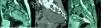

MétodosRealizamos un análisis retrospectivo de 19 casos de tumores neurogénicos de la región sacra diagnosticados y operados en nuestro centro, de los cuales ocho eran hombres y 11 mujeres, registrando una edad media al diagnóstico de 51 años (con un rango de edades entre 25 y 78 años). Seis se encontraban asintomáticos y fueron diagnosticados incidentalmente, mientras que la mayoría (11 pacientes) presentaban dolor lumbar acompañado de otros síntomas: dolor irradiado a miembros inferiores (MMII), dolor pélvico, alteraciones sensitivas y pérdida de fuerza en MMII. Dos pacientes presentaban otro síntoma principal al diagnóstico: dolor pélvico y en miembro inferior izquierdo (MII). A todos los pacientes se les realizó como mínimo una prueba de imagen (RM/TC). Nueve pacientes tenían tumores limitados al sacro o con extensión posterior, practicándose una intervención por vía posterior. En seis se realizó un abordaje exclusivamente por vía anterior debido a la localización presacra de la tumoración; y en cuatro de ellos fue preciso un abordaje tanto anterior como posterior.

MethodsWe conducted a retrospective analysis of 19 cases of patients with neurogenic tumors in the sacral area who were diagnosed and underwent surgery at our center. Of them, 8 were male and 11 were female. They had a mean age at diagnosis of 51 years (with an age range of 25-78 years). Six patients were asymptomatic and were diagnosed incidentally, while the majority (11 patients) presented with lumbar pain accompanied by other symptoms: pain radiating to the legs, pelvic pain, sensory alterations and loss of strength in the legs. Two patients presented with another primary symptom on diagnosis: pain in the pelvic region and in the left leg. All patients underwent a least one imaging test (MRI/CT scan). Nine patients had tumors limited to the sacrum or with subsequent spread, with surgery via the posterior route. In 6 cases, an exclusively anterior approach was employed owing to the pre-sacral location of the tumor; 4 cases required both an anterior and posterior approach.